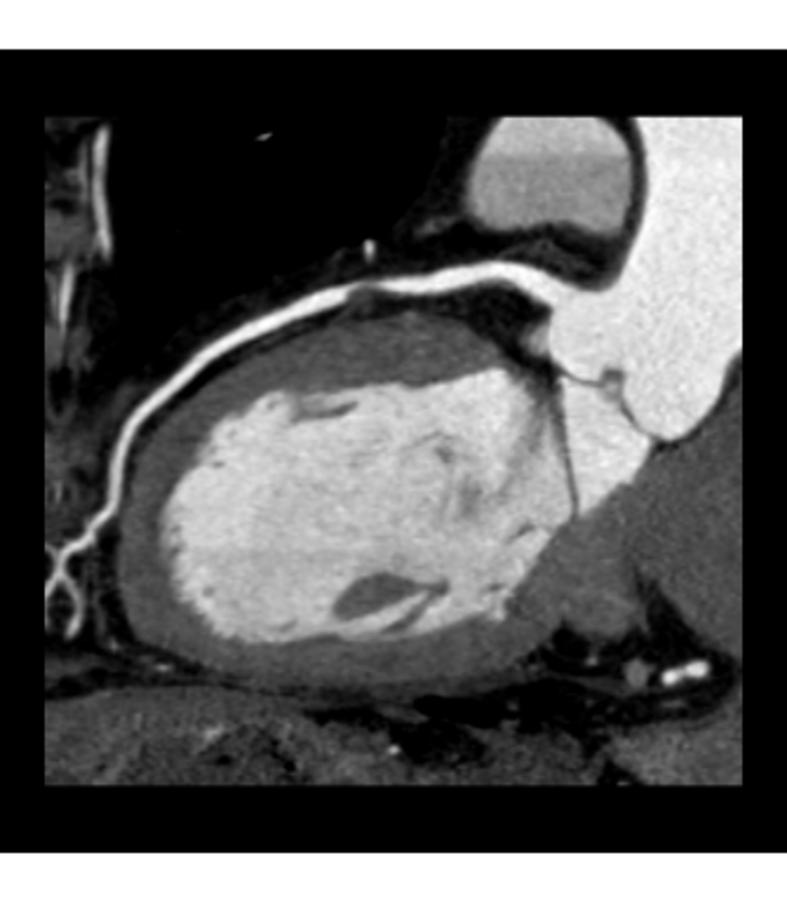

Die schwere Verkalkung des Ramus interventricularis anterior (RIVA, farbliche Markierung rechtes Bild) heißt nicht, dass auch eine relevante Stenose vorliegt. Die schwere Verkalkung des Ramus interventricularis anterior (RIVA, farbliche Markierung rechtes Bild) heißt nicht, dass auch eine relevante Stenose vorliegt. © Privatdozent Dr. Andreas Rolf, Kardiologie am Herzzentrum, Kerckhoff-Klinik, Bad Nauheim

Trotz des Kalks lässt sich diese (Stenose) mit dem modernen CT-Scanner sicher ausschließen, was vor allem die multiplanare Rekonstruktion desselben Gefäßes verdeutlicht. Trotz des Kalks lässt sich diese (Stenose) mit dem modernen CT-Scanner sicher ausschließen, was vor allem die multiplanare Rekonstruktion desselben Gefäßes verdeutlicht. © Privatdozent Dr. Andreas Rolf, Kardiologie am Herzzentrum, Kerckhoff-Klinik, Bad Nauheim